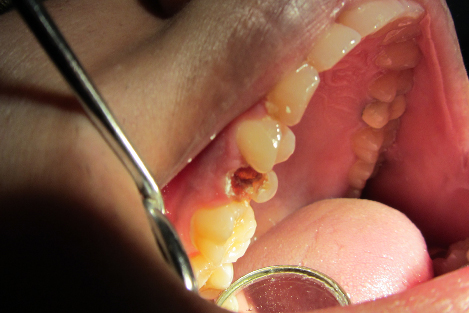

Post n Core